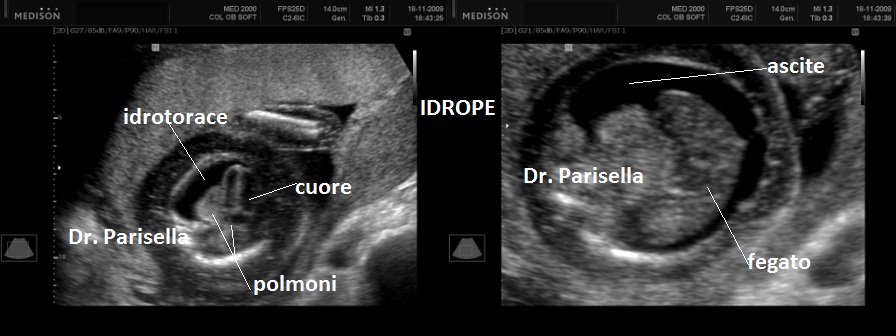

All'ecografia prenatale si riscontra ipoplasia toracica (torace stretto e coste corte), rizomelia lieve-moderata e frequentemente  displasia renale policistica.